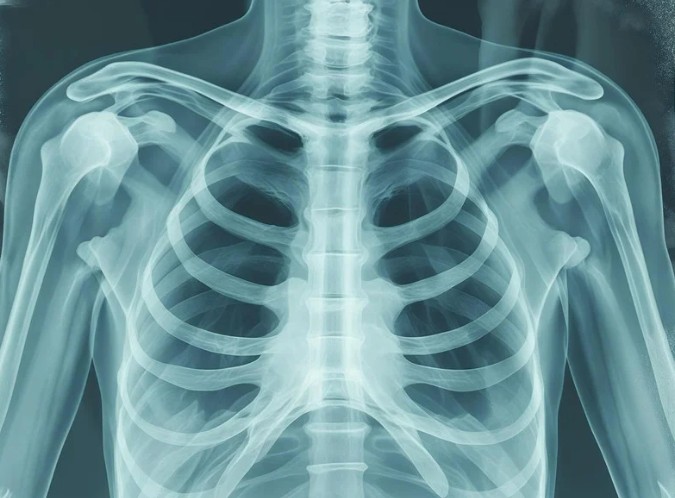

Digital X-Ray

High-resolution digital radiography with instant image availability, reduced radiation exposure, and superior image quality for accurate diagnosis.

Chest X-Ray

Comprehensive chest imaging for detecting pneumonia, tuberculosis, lung cancer, heart enlargement, and other thoracic conditions with rapid results.